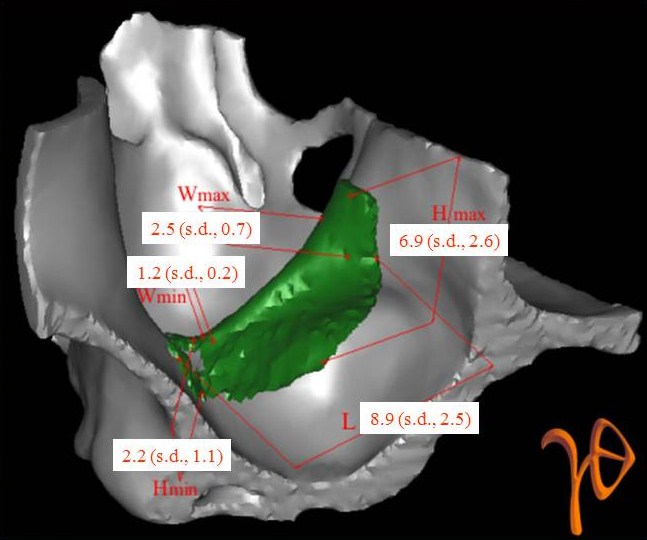

Οι πιο συχνές βλάβες από ερεθισμό στο στόμα είναι τα αντιδραστικά ινώματα (Εικόνες 4 και 5).

Εικόνα 4. α. Ίνωμα της υπερώας από χρόνιο ερεθισμό ολικής οδοντοστοιχίας (βέλος), β. Μετά την χειρουργική του αφαίρεση.